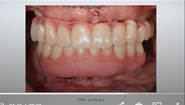

Fig 30. Retracted view of the patient’s dentition at 1 week postoperatively.

Figure 30